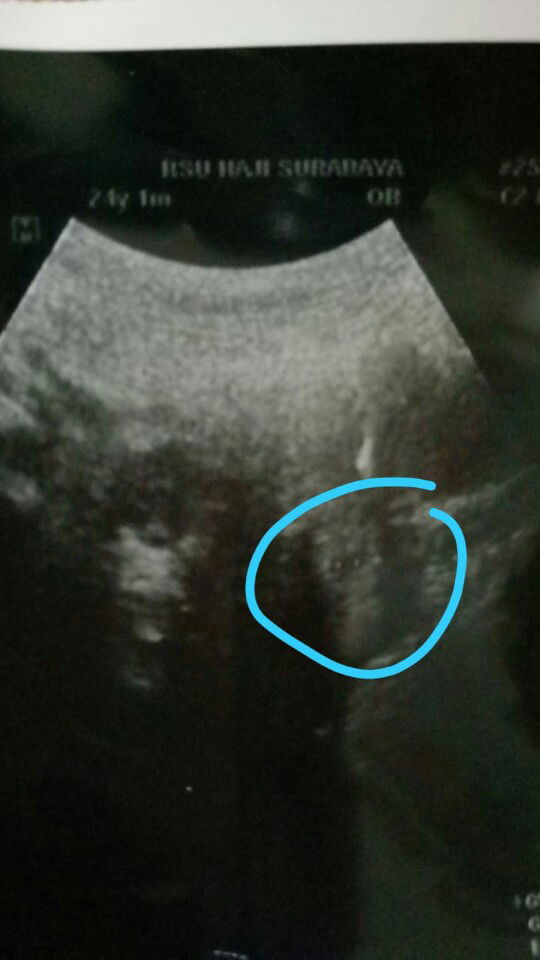

ini kantong kehamilan atau bukan?

kata dokter 6w... tp saya pakai kb IUD... setelah kontrol kb ada semacam kantong kehamilannya kata dokter...